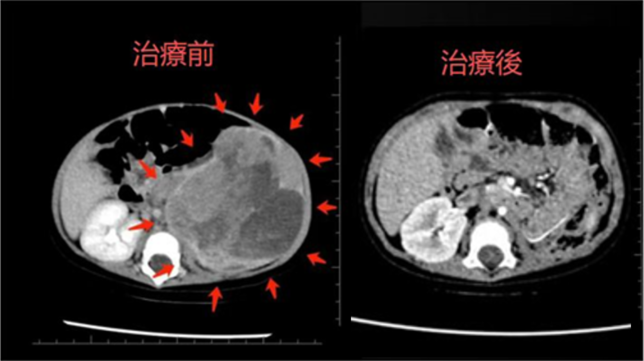

由于婴儿的生理特点,传统的放疗手段可能对正常组织,尤其是脏器,造成不可逆的损伤。因此,质子治疗成为了最佳选择。由清水翔星教授牵头,医院团队为患儿制定了个性化的质子治疗方案,利用质子束的独特「布拉格峰」特性,精准地将放射剂量集中于肿瘤靶区,最大限度减少对正常组织的伤害,尤其是在腹盆腔和脊柱区域的保护效果非常显著。

清水翔星教授表示:「在这项研究中,医院的创新主要体现在以下几个方面,首先是极低龄婴儿质子治疗的首次尝试。该病例是全球首例在 6 个月以内婴儿中成功实施腹盆腔质子治疗的案例。这个突破为婴儿肿瘤治疗提供了全新的视角,也为今后的类似病例提供了宝贵的临床经验。」

「团队特别注重精准剂量控制。采用 IMPT(Intensity Modulated Proton Therapy)技术,严格控制重要脏器的辐射剂量,尤其是对患儿唯一功能肾的辐射剂量,确保其平均剂量控制在<1.5 Gy,从而最大限度地保护了肾脏的功能。」

值得高兴的是,经过 1 年的随访,患儿无肿瘤复发,肾功能和肝功能持续保持在正常范围,进一步验证了质子治疗的长期安全性与疗效。这一结果不仅证明了治疗的有效性,也为质子治疗在高风险婴幼儿群体中的应用提供了更强的支持。